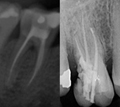

• Root Canal Treatment (Endodontics) Rawatan akar

• Front teeth or back teeth